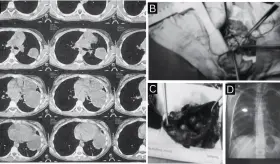

La reactivación ocurrió en el contexto de un aumento en la inmunosupresión, específicamente con el incremento del micofenolato mofetilo (MMF).